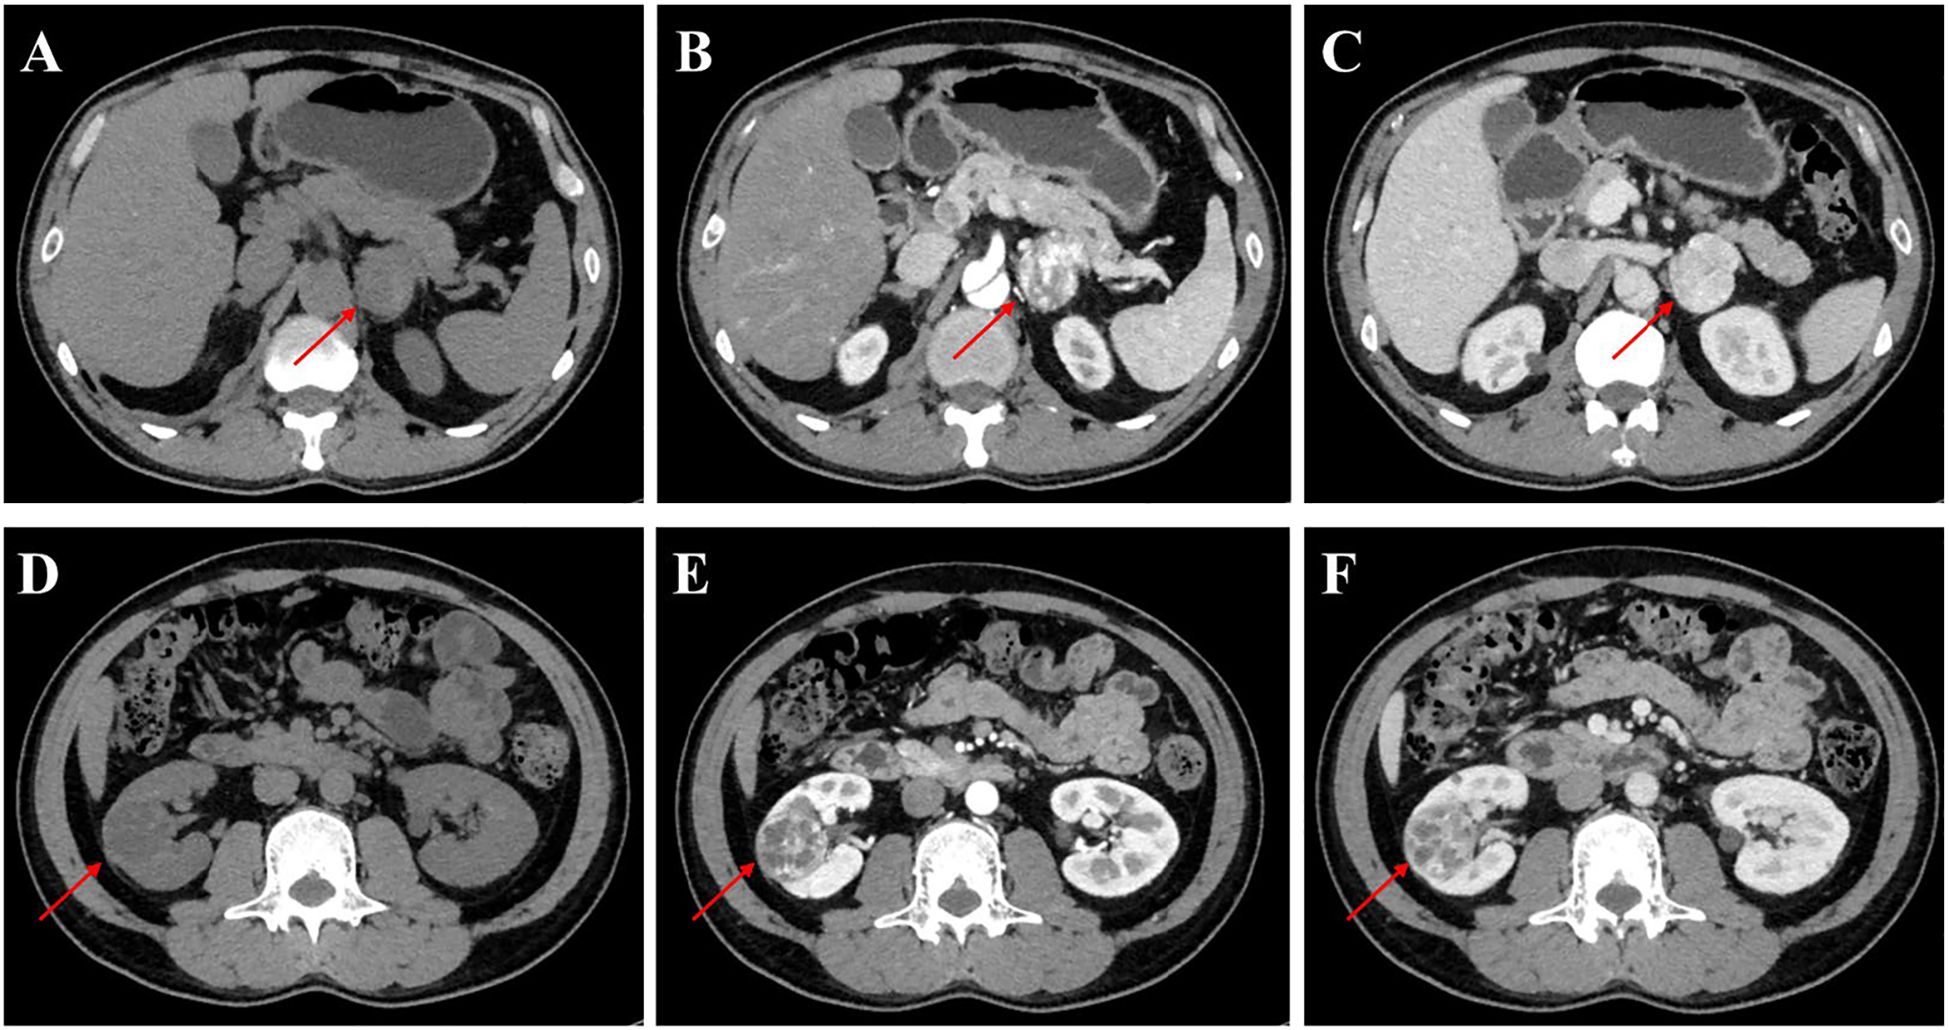

The patient was admitted to our department for further management of progressively enlarging left adrenal and right renal masses. A recent contrast-enhanced abdominal CT scan demonstrated substantial growth of the lesions, with the left adrenal mass measuring 4.1×3.5 cm and the right renal mass 3.5×3.5 cm (Figure 2). Upon adjusting the window width during image analysis, an additional renal mass measuring 1.3 × 1.4 cm was identified in the right kidney (Supplementary Figure 1). The imaging characteristics were consistent with pheochromocytoma and RCC. Subsequent serological evaluation revealed markedly elevated normetanephrine levels (Supplementary Table 1), which definitively confirmed the diagnosis of pheochromocytoma. Additionally, multiple hepatic, pancreatic and bilateral renal lesions were observed in the liver, pancreas and bilateral kidneys, radiologically consistent with hepatic hemangiomas and simple pancreas/renal/hepatic cysts (Figure 3, the number of renal cysts > 30).

Figure 2. Contrast-enhanced CT imaging of the left adrenal gland and kidney in the patient. (A-C) Axial CT images of the left adrenal gland: (A) Non-contrast phase demonstrating a well-circumscribed mass (arrow) measuring 4.1×3.5 cm, (B) Arterial phase (AP) showing heterogeneous enhancement of the adrenal lesion, (C) Venous phase (VP) with persistent contrast retention in the mass. (D-F) Coronal CT images of the left kidney: (D) Unenhanced scan revealing a 3.5×3.5 cm hypodense renal mass (arrowhead), (E) AP highlighting peripheral nodular enhancement, (F) VP demonstrating washout pattern characteristic of RCC.